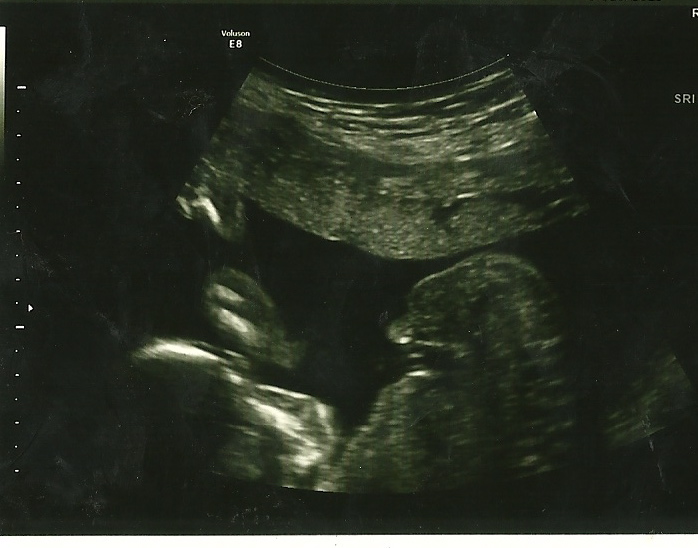

I was given this picture below and it said, "its a boy"! no potty shot or explanation. Is this a boy? 19 weeks?Attachment 12680

Feel silly even posting this, but just can't come to grips with 4 boys. GD is awful! Hoping that more confirmation will allow me to move forward.